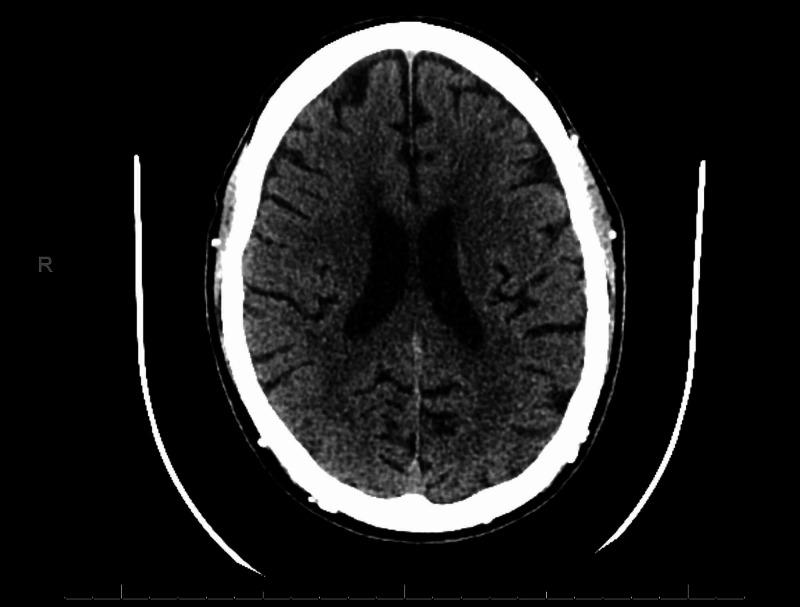

There are a few cases of valacyclovir-associated neurotoxicity (VAN) reported. This case report documents a case of a 55-year-old male presenting with emotional lability or pseudobulbar affect as the predominant or sole manifestation of VAN. A failure to adjust valacyclovir's dose for herpes simplex infection in the setting of dialysis-dependent end-stage renal disease (ESRD) preceded VAN in this patient. The patient presented with involuntary and uncontrollable outbursts of emotion. Computerized tomography (CT) scan identified no underlying cause. A complete neurological examination with cognitive assessment was performed, with no abnormalities. He benefited from the use of aggressive peritoneal dialysis (PD) that was employed to enhance valacyclovir's clearance in this case of intractable VAN. On discharge, the patient was back to baseline mental function. Traumatic brain injury, neoplasm, vascular lesions, metabolic abnormality, neurological disease, herpetic encephalitis, and disorders of mood were ruled out. This led to the hypothesis of encephalopathy due to valacyclovir intoxication. Given that the clinical manifestations were related to ESRD, a dose-adjustment of valacyclovir is imperative in the setting of ESRD to prevent VAN. Our case presents important clinical variations. Firstly, our patient demonstrates that VAN may present with no focal neurological impairment, but pseudobulbar affect. Secondly, aggressive PD was useful in this case for the treatment of VAN as opposed to hemodialysis. We believe that it cleared valacyclovir resulting in the resolution of symptoms.

摘要